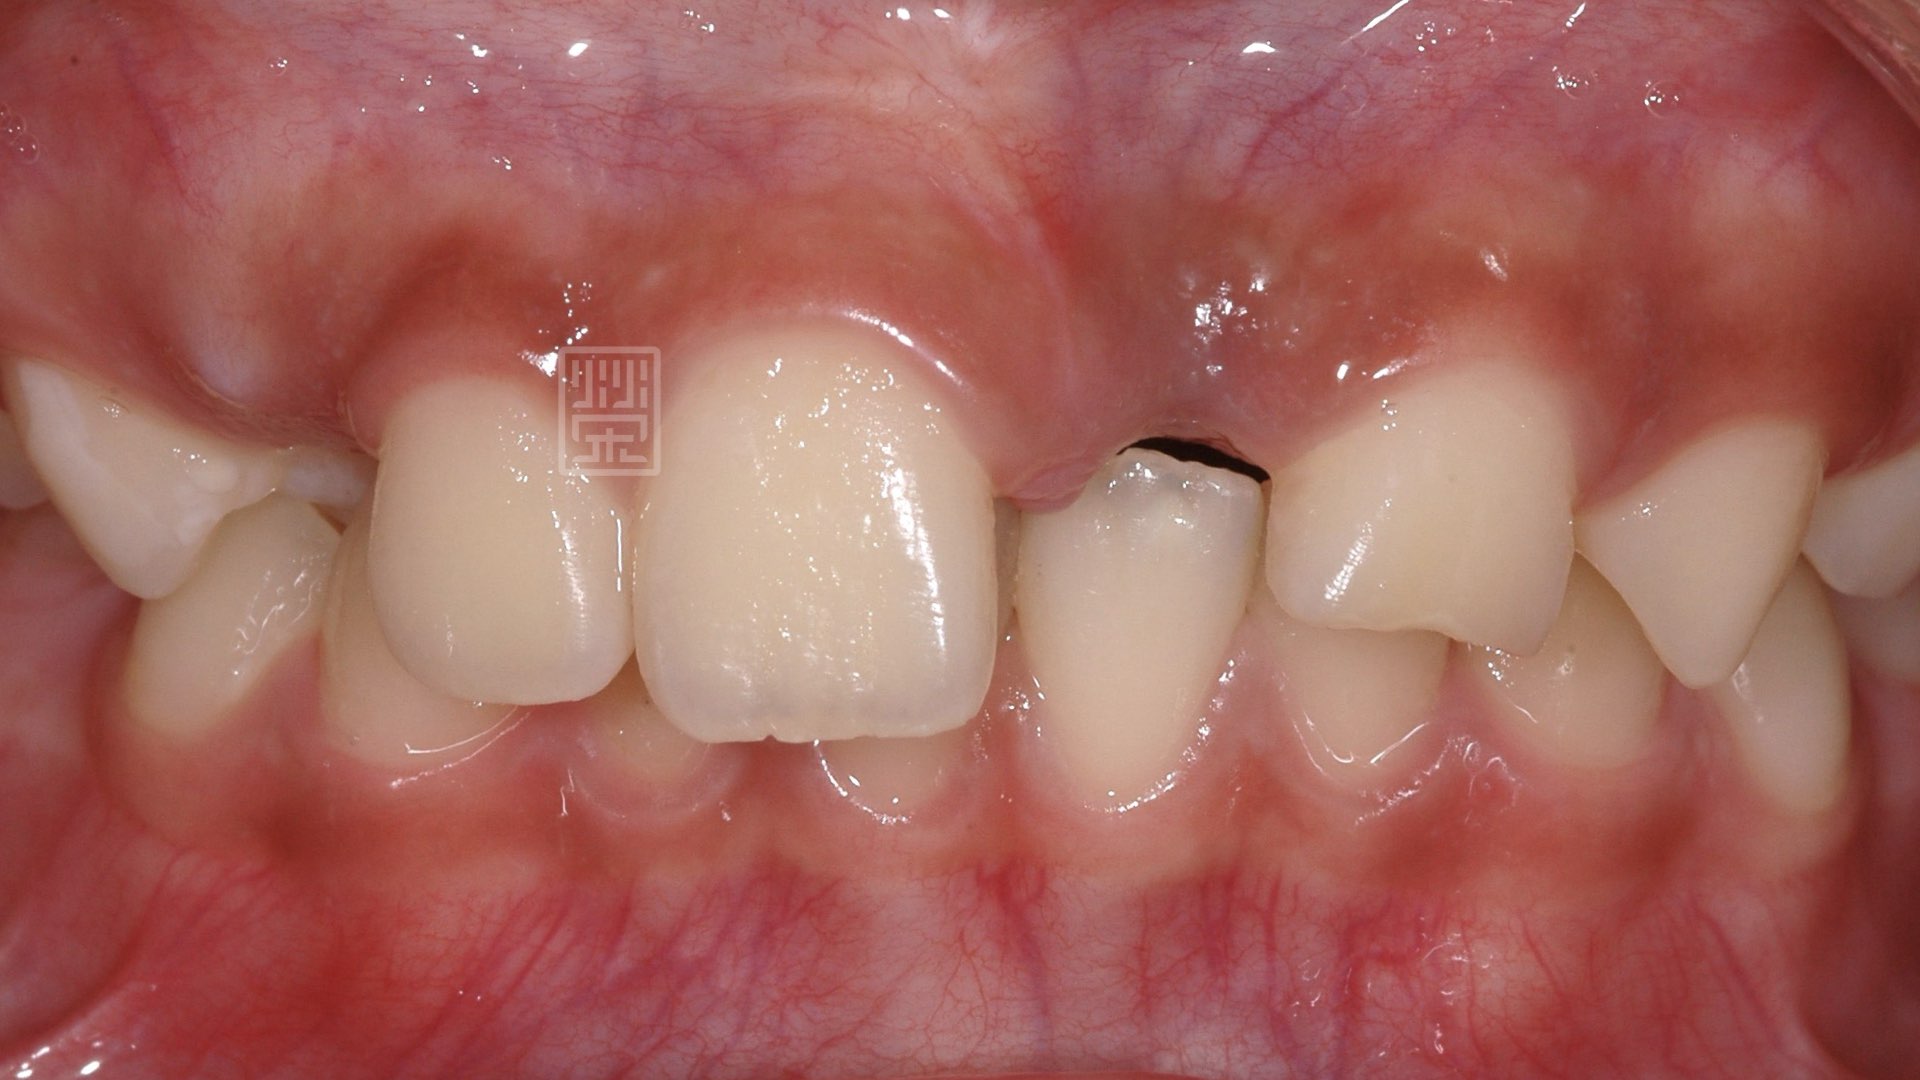

顎側輕微修磨製作馬利蘭牙橋

馬利蘭牙橋製作過程